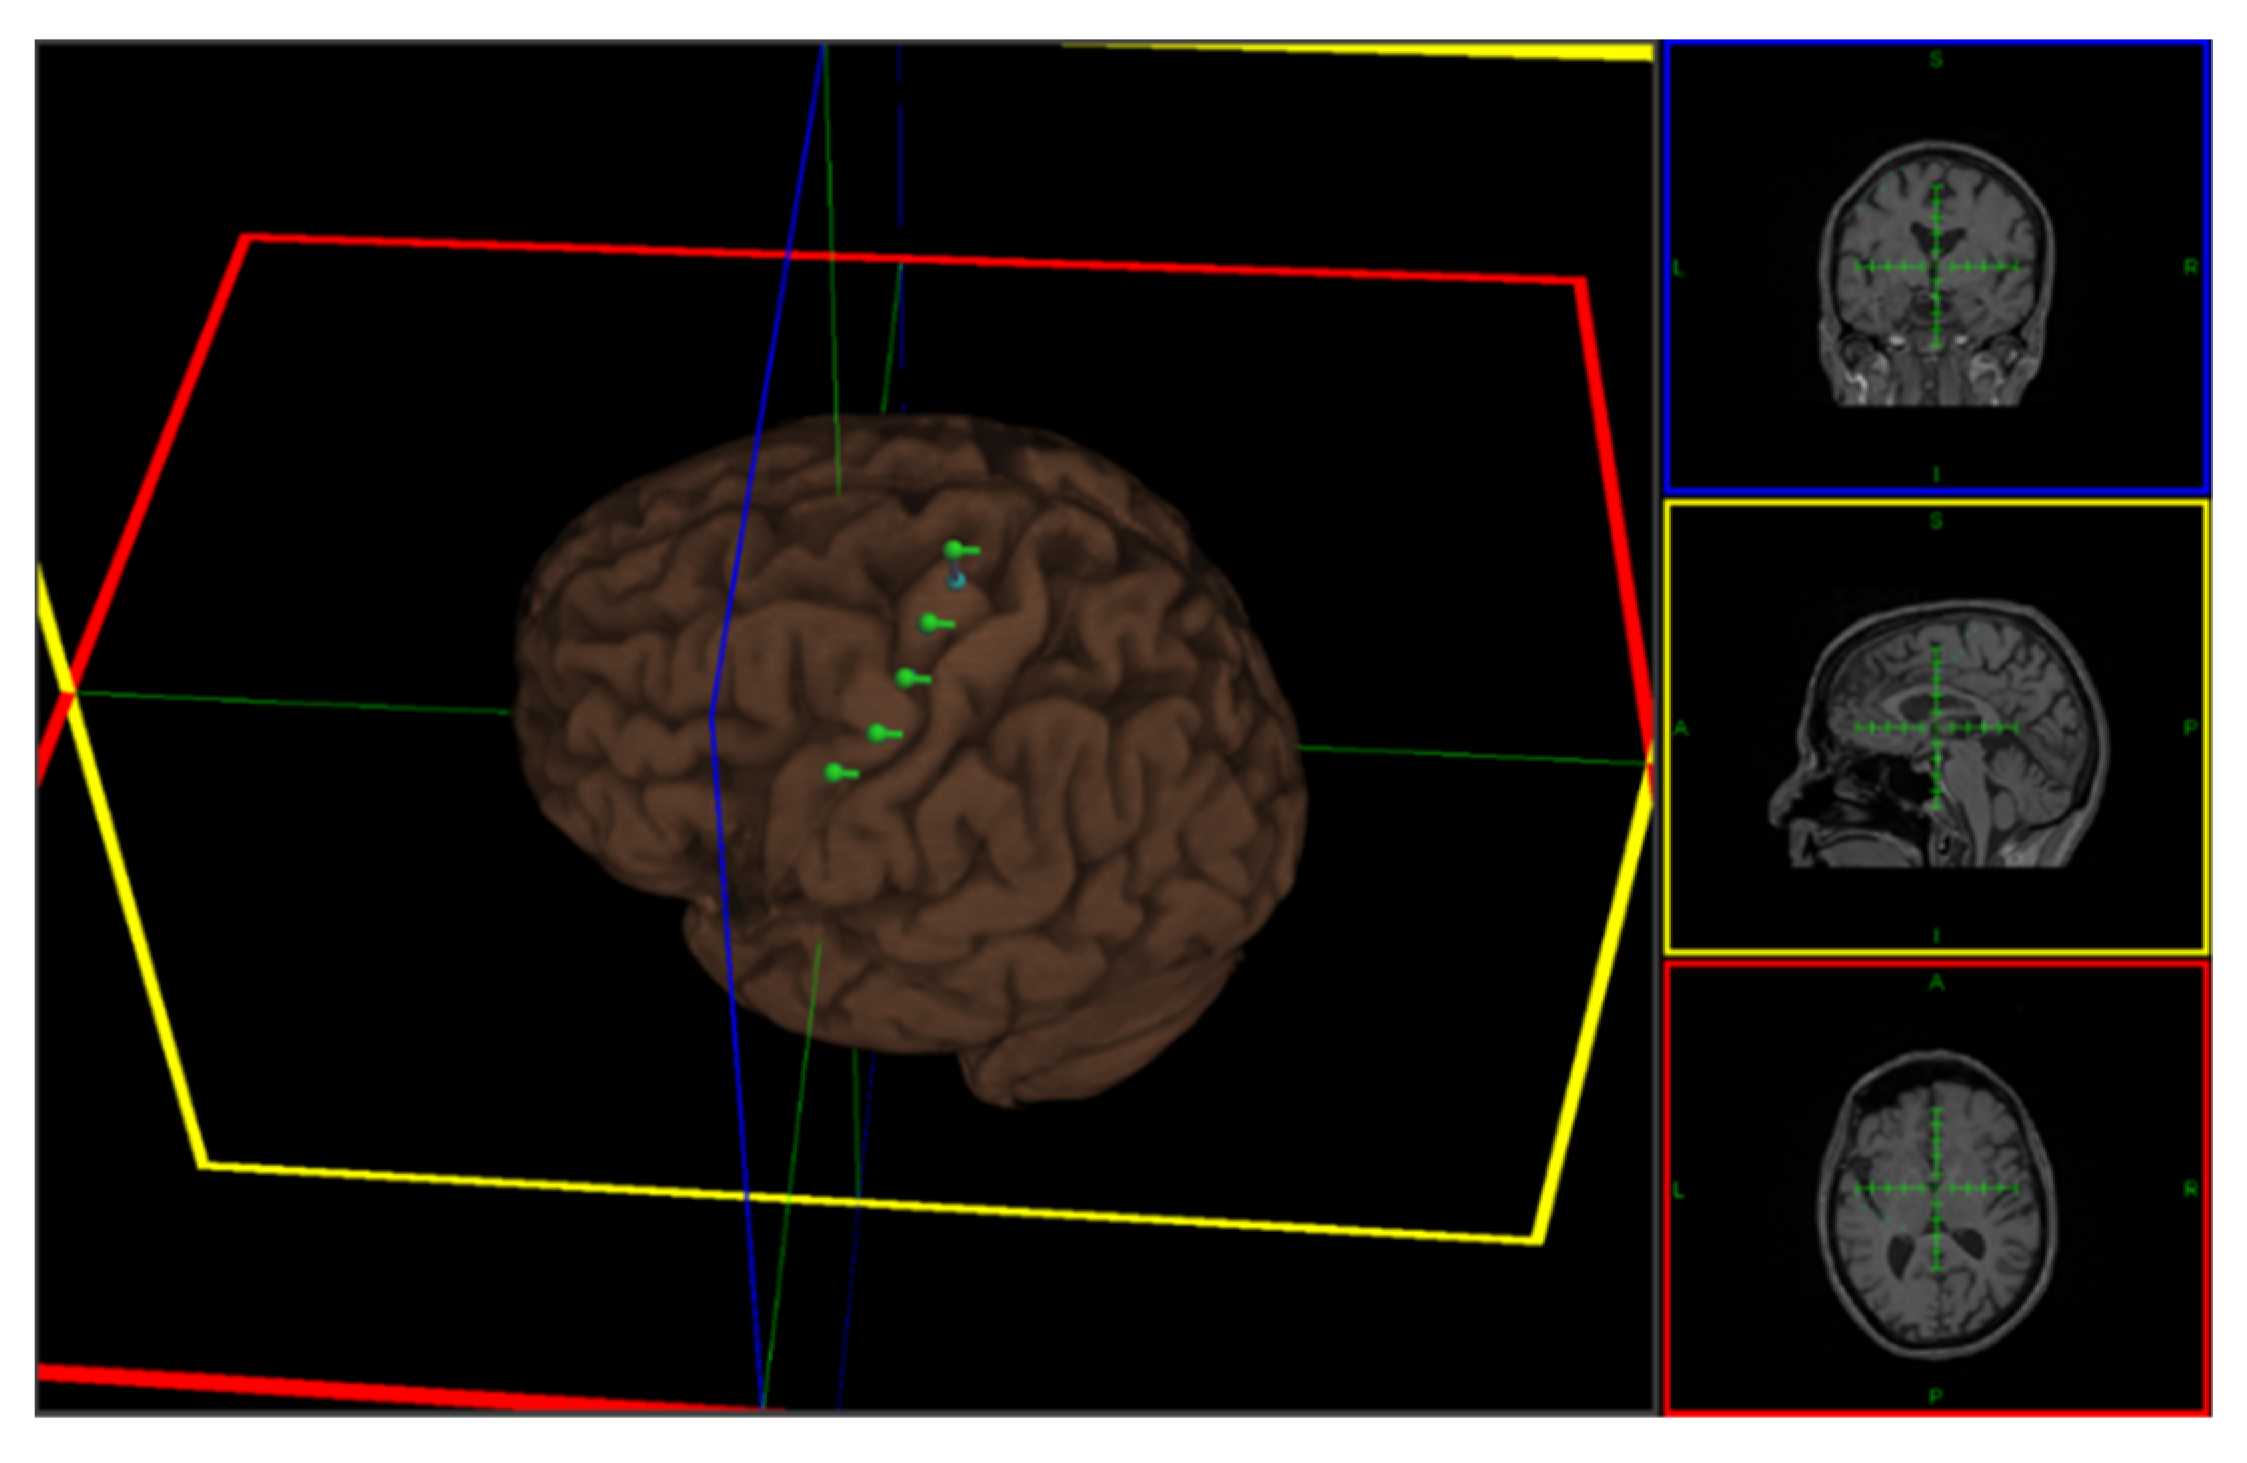

2.3. Repetitive Transcranial Magnetic Stimulation (rTMS)